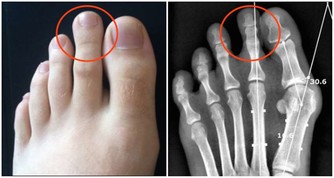

(4)牙齦和鼻子出血

很多人都經歷過牙齦流血,或者鼻子出血,如果是頻繁出血,而且量大又止不住血,就要警惕肝病。

當肝細胞損傷後,肝臟產生凝血因子的功能下降,凝血機制就會發生障礙。

肝病患者的出血,可能是刷牙時牙齦出血,或者活動鼻子時出血,也可能是吃東西時,食物上出現血痕。

肝病越嚴重,出血現象越嚴重。